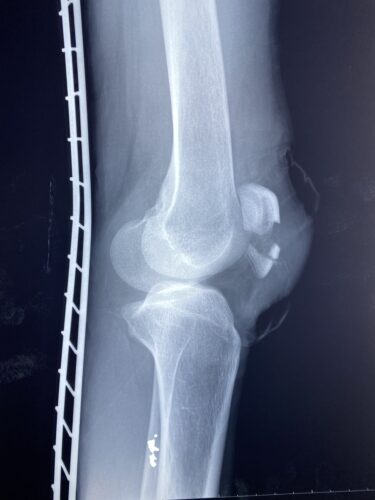

【整骨研究会「賜恩」での症例発表】

肘関節前方脱臼の1症例について